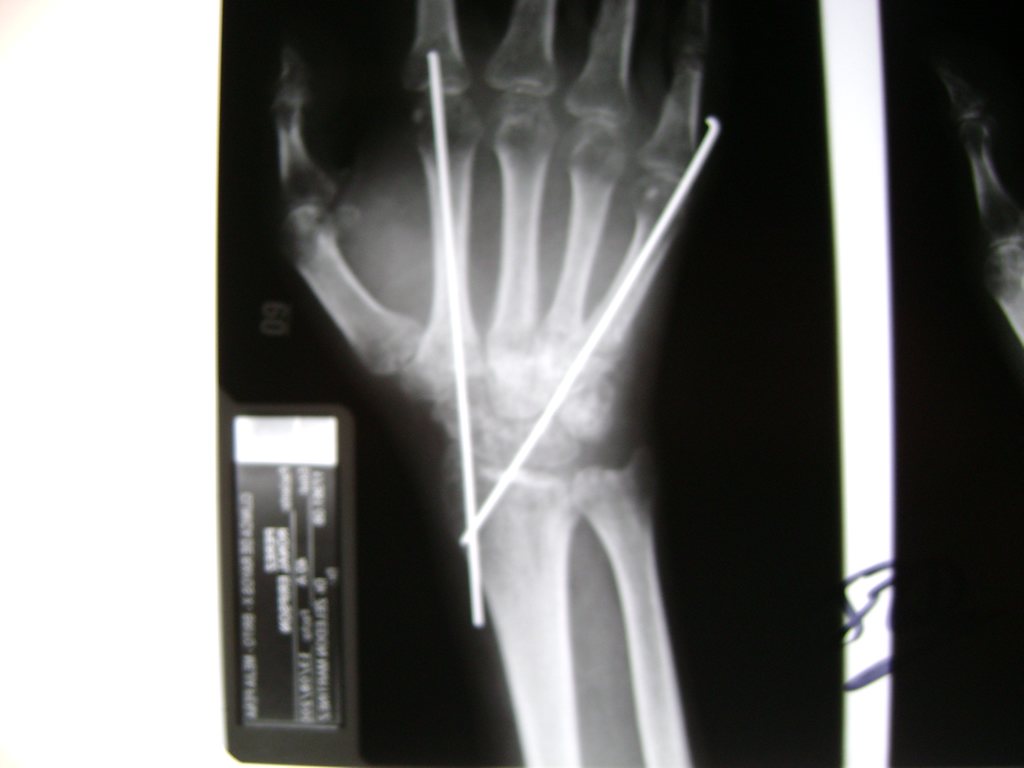

Cirugía de Fémur - Cirugías de Muñecas y Manos

Los procedimientos más comunes en cirugía de la mano son aquellos destinados a reparar traumatismos, incluyendo lesiones de tendones, nervios, vasos sanguíneos, y articulaciones; huesos fracturados; y quemaduras, cortes, y otros daños de la piel.